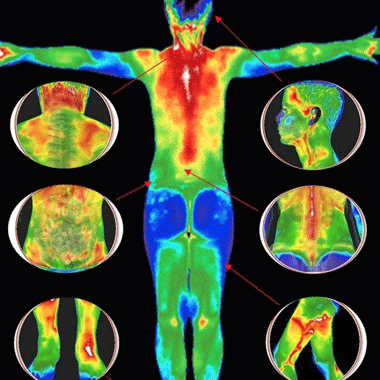

Orvosi IBR-SYSTEM® ekcéma diagnosztika és kezelési terv

Állandóan viszket, szárad, fáj, hólyagosodik? Az ekcéma minden évszakban kellemetlen, különösen jó időben, amikor el sem tudjuk takarni a nyomait. Az ekcémás megbetegedések száma napjainkban rohamosan nő. Ajánlatunk egy olyan speciális terápiát tartalmaz, mely révén fájdalom és mellékhatások nélkül hatékonyan kezelhető a kellemetlen bőrbetegség. Ezzel az eljárással az ekcémás betegek 71%-a meggyógyítható.